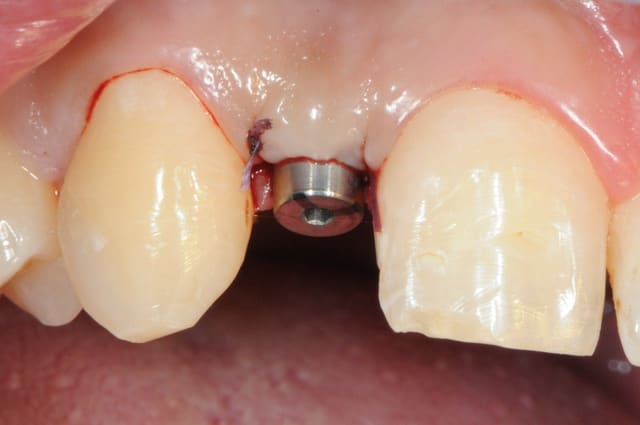

je reviens sur ce cas que j'ai un peu délaissé...

-cicatrisation

-mise en place vis de cica petit diamètre

-ensuite on augmente le diamètre en conservant et en gonflant les tissus gingivaux

-cicatrisation de la première vis de cica,

-diamètre plus gros pour la vis de cica

- pilier pour la provisoire

- provisoire moule ION

- ajustage

- polissage soigneux